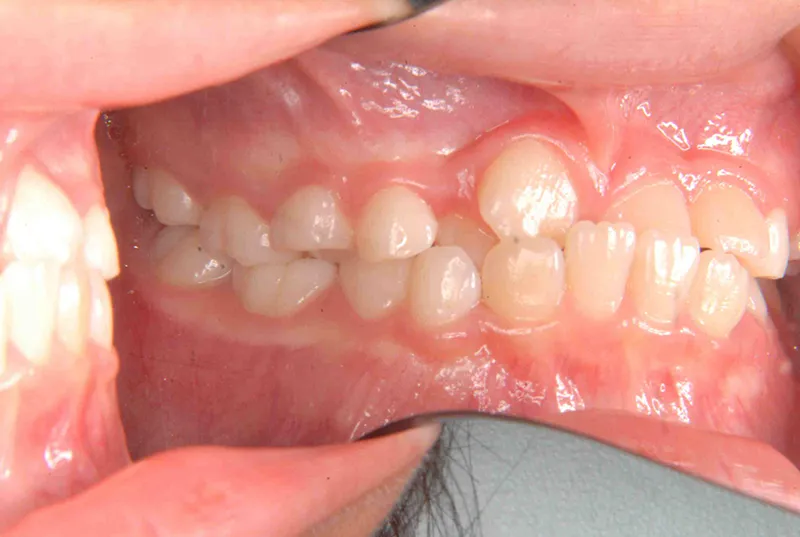

初診時年齢 小学校2年生 (女性) 主訴 受け口・がたがた

診断名 埋伏歯・反対咬合・叢生 装置名

特徴 ゆがんで生えている

上の歯と下の歯で舌をはさむ癖がある

状態 永久歯が生える隙間がない(叢生)

受け口(下顎前突/反対咬合)

歯が埋まっている/歯がない(埋伏歯)

受け口で、ガタガタが有りました。

レントゲンを撮ってみると犬歯の萌出方向がずれていました。

初診